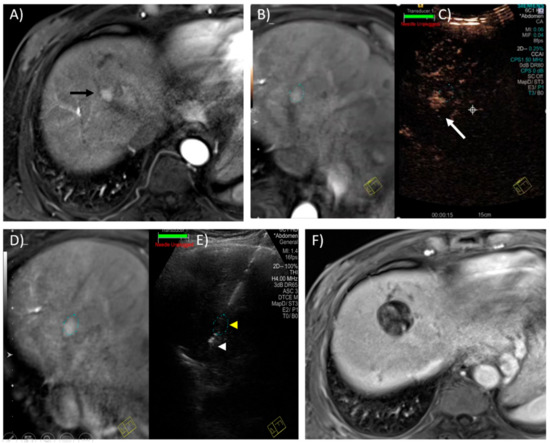

- Hoffmann, R.; Rempp, H.; Keßler, D.-E.; Weiß, J.; Pereira, P.L.; Nikolaou, K.; Clasen, S. MR-guided microwave ablation in hepatic tumours: Initial results in clinical routine. Eur. Radiol. 2016, 27, 1467–1476. [Google Scholar] [CrossRef]

- Clasen, S.; Rempp, H.; Hoffmann, R.; Graf, H.; Pereira, P.L.; Claussen, C.D. Image-guided radiofrequency ablation of hepatocellular carcinoma (HCC): Is MR guidance more effective than CT guidance? Eur. J. Radiol. 2014, 83, 111–116. [Google Scholar] [CrossRef] [PubMed]

- Rempp, H.; Loh, H.; Hoffmann, R.; Rothgang, E.; Pan, L.; Claussen, C.D.; Clasen, S. Liver lesion conspicuity during real-time MR-guided radiofrequency applicator placement using spoiled gradient echo and balanced steady-state free precession imaging. J. Magn. Reson. Imaging 2013, 40, 432–439. [Google Scholar] [CrossRef]